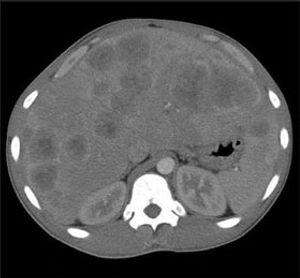

Right upper quadrant pain of 24 hours’ duration prompted a 20-year-old man with a history of gastritis to seek medical attention. The pain was sharp and nonradiating, with no alleviating or aggravating factors. The patient occasionally consumed alcohol and regularly smoked cigarettes (tobacco and marijuana). He denied nausea, vomiting, diarrhea, and diaphoresis. Right upper quadrant pain of 24 hours’ duration prompted a 20-year-old man with a history of gastritis to seek medical attention. The pain was sharp and nonradiating, with no alleviating or aggravating factors.